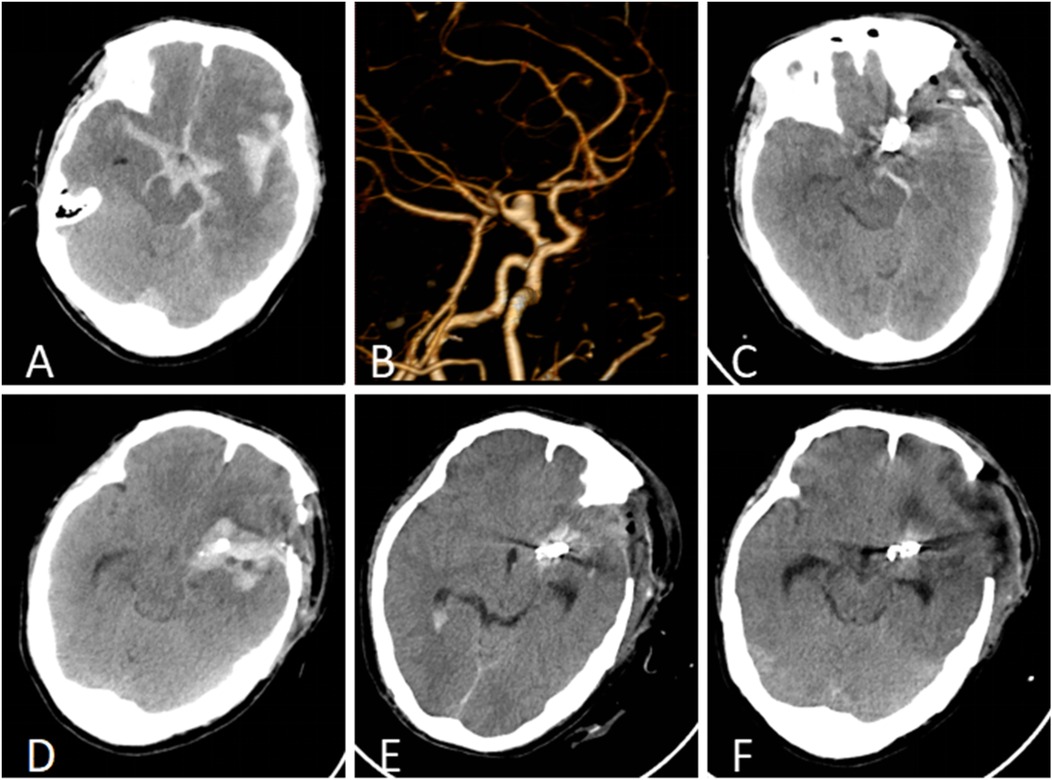

A 50-year-old male patient was admitted with a complaint of a persistent headache lasting for three hours. His medical history was notable for a 20-year history of smoking, with no evidence of hypertension or diabetes. Upon physical examination, the patient was found to be alert and oriented, with a Glasgow Coma Scale (GCS) score of 15 (E4V5M6). The pupils were bilaterally isocoric at 3.0 mm and exhibited intact light reflexes. Signs of meningeal irritation were absent, and no significant neurological deficits were detected. Cranial computed tomography (CT) and computed tomography angiography (CTA) revealed a subarachnoid hemorrhage and an aneurysm of the left internal carotid artery at the ophthalmic segment (Figures 1A,B). He was classified as Hunt-Hess grade II and modified Fisher grade III. The patient underwent a craniotomy for aneurysm clipping. The initial postoperative CT scan of the head demonstrated post-clipping alterations and a marked reduction in the intracranial hematoma relative to prior imaging (Figure 1C). Following this, the patient was administered continuous lumbar drainage of hemorrhagic cerebrospinal fluid (CSF) in conjunction with appropriate supportive care. Three weeks postoperatively, the patient demonstrated a favorable recovery and was discharged without complications. However, 10 days after discharge, the patient was readmitted in a state of sudden coma. The left pupil was noted to be dilated with an absent light reflex. An emergency cranial CT scan revealed the formation of a hematoma in the left frontotemporal lobe, indicating the possibility of rebleeding at the surgical site (Figure 1D), the patient underwent an emergency craniotomy for the evacuation of a hematoma. Intraoperative exploration revealed a recurrent and reruptured aneurysm located in the ophthalmic segment. Successful aneurysm clipping was achieved, along with hematoma evacuation and decompressive craniectomy (Figure 1E). The procedure was completed without complications. After an uncomplicated clinical recovery, the patient was discharged. The pre-discharge follow-up cranial CT scan showed postoperative changes in the brain, with no other significant abnormal findings observed (Figure 1F). Fifteen days post-discharge, the patient exhibited cognitive decline and left-sided weakness. A readmission cranial CT scan revealed a cystic lesion located dorsal to the right ambiens cistern and medial to the parahippocampal gyrus (Figure 2A). Serial imaging conducted at a three-month interval demonstrated progressive enlargement of the cystic lesion (Figure 2B). Subsequent cranial magnetic resonance imaging (MRI) excluded the presence of gliomas and cholesteatomas (Figures 2C,D). One year later, amidst ongoing neurological deterioration, follow-up cranial CT indicated further expansion of the cystic lesion, accompanied by a significant mass effect (Figures 3A,B). Neuroendoscopic exploration was conducted under general anesthesia, during which a cortical fenestration of the temporal lobe was created to facilitate access to the cystic cavity. Intraoperative observations revealed a thickened cyst wall under high tension with evidence of vascular proliferation. The cystic fluid was colorless and transparent, lacking hemosiderin deposition (Figures 4A–C). An arachnoid cyst was suspected intraoperatively, prompting partial resection of the cyst wall and the creation of a lateral ventriculostomy. The fistulous opening measured approximately 2.5 cm in diameter, facilitating communication with the lateral ventricle (Figure 4C). Histopathological analysis of the cyst wall confirmed the diagnosis of an arachnoid cyst (Figure 5). Following the surgical procedure, the patient demonstrated a gradual enhancement in left-sided motor weakness and cognitive abilities. At the three-month follow-up, both motor and cognitive functions had nearly returned to baseline levels. The GCS score was recorded at 15 (E4V5M6). The latest cranial MRI revealed a substantial reduction in cyst volume, accompanied by a complete resolution of the mass effect (Figures 3C,D).

Figure 1. (A) Cranial CT identified a subarachnoid hemorrhage and a hematoma within the left fissure cistern. (B) CTA revealed an aneurysm in the ophthalmic segment of the left internal carotid artery. (C) The initial postoperative CT follow-up indicated a reduction in intracranial hemorrhage following cerebral aneurysm clipping. (D) Rebleeding was detected 10 days post-discharge, with an emergent cranial CT scan revealing a hematoma in the left frontotemporal region. (E) The initial follow-up CT after the second surgical intervention confirmed successful clipping of the cerebral aneurysm and substantial resolution of the temporal hematoma. (F) At the time of discharge, postoperative cranial CT demonstrated postsurgical changes without signs of hydrocephalus or cyst formation.